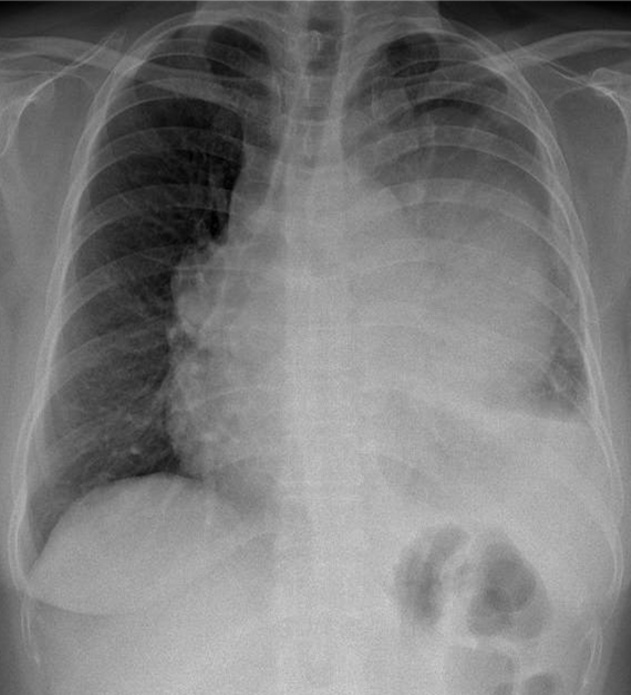

Hãy phân tích tình huống nữ 59 tuổi

1-U trung thất (T) 2-Tràn dịch màng phổi (T)